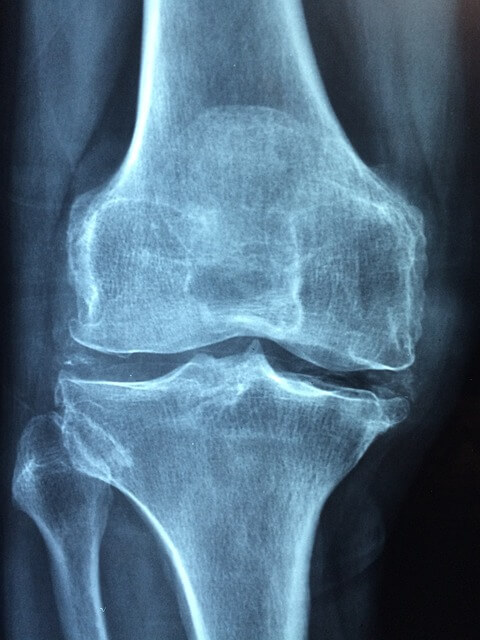

치료 방법

관절염의 치료는 우선 운동이나 무거운 것을 피하여 최대한 안정을 유지한다.

그 외로 슬개골 연화증이나 연골에 손상이 간 경우는

관절에 부담을 줄이기 위해 물리치료와 체중감량,

자세교정과 주사치료를 병행하지만 연골이 닳아 없어지거나

그 치료방법도 효과를 보기 어려운 경우는

인공관절 치환술과 절골술을 병행하여 치료합니다.

또 무릎이나 연골은 퇴행성 질환이기 때문에 완치보다는

장기적인 관리가 훨씬 더 중요합니다.